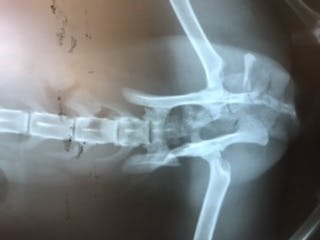

先生は見てすぐに「骨折してる」と仰い、レントゲンを撮ると骨盤が骨折していました。「交通事故だよ」とも仰いました。

また「お腹から折れた骨が飛び出てそれがまたお腹に戻ったんだね。」とも仰いました。

今、壊死してしまった皮膚と化膿している所が広範囲の為、縫合手術はせずに新しい皮膚が下から盛り上がって来るまで毎日皮膚の洗浄をし、点滴や注射をしながら栄養補給をし、皮膚の再生を待ちつつ、今後体力がついてから骨折の手術をするそうです。

ご支援頂いた金額は入院費(1日 5,500円)×入院日数(現在入院中)、通院費、初診料1,650円、診察料(1回)825円×通院日数、処置料550円×通院日数、レントゲン検査費4,400円、血液検査費、猫三種混合ワクチン費6,050円、尻尾切除費11, 000円、骨折手術費110, 000円、骨折手術後の入院費(まだ不明)、点滴料(1回)1,100円、注射料(1本)1,100円、内用薬費、療法食代、避妊手術費25,300円にあてさせて頂きます。

残念ながら尻尾がダメになってしまったそうなので、尻尾の切除手術を行い、体力がついて来てから骨盤骨折の手術を行います。